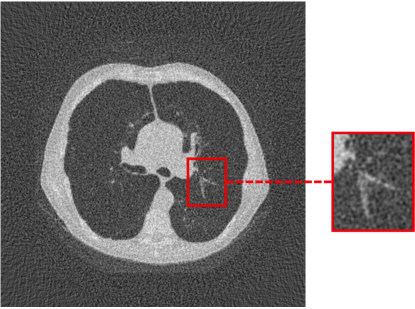

To assess the performance of the HLSF, four phantoms with structural patterns of different complexity have been considered (Fig. 4). PH-1 in Fig. 4(a) is the segmentation of a reconstructed slice of mouse lung tissue at micrometer scale. PH-2 in Fig. 4(b) is a multilevel segmentation of a MRI scan of a human brain. PH-3 in Fig. 4(c) is a multilevel segmentation of a CT slice of a human lung. PH-4 is the well-known Shepp-Logan phantom [16].

Refer to caption

(a) PH-1

(b) PH-2

(c) PH-3

(d) PH-4

Figure 4: Set of simulated data used to benchmark the HLSF. PH-1 has 784 ×\times 784 pixels; PH-2 has 592 ×\times 592 pixels; PH-3 has 500 ×\times 500 pixels; PH-4 has 512 ×\times 512 pixels.